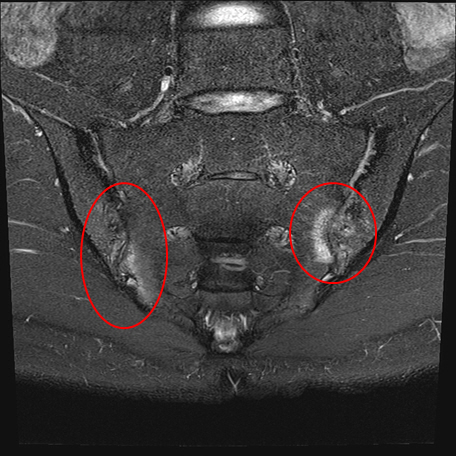

ankylosing spondylitis is one of the chronic softening diseases of spondyloarthritis. In addition to the spine or joints, it can cause diseases in various organs of the body such as the eyes, skin, and gastrointestinal tract, so it is not a simple musculoskeletal disease, but a systemic disease. As a result of imaging tests, if there is sacroiliac arthritis (a disease that causes inflammation of the joints where the sacrum, which is the bone below the spine, and the ilium, which is the bone of the bone, meet the definition of spondyloarthritis, it is defined as ankylosing spondylitis.

Professor Lee Ju-ha said "Strong spondylitis is prone to misdiagnosis because it shows symptoms similar to those of a lumbar disc in the early stages."If an experienced rheumatologist discriminates symptoms and performs appropriate imaging tests to detect sacroiliac arthritis, early diagnosis is possible."